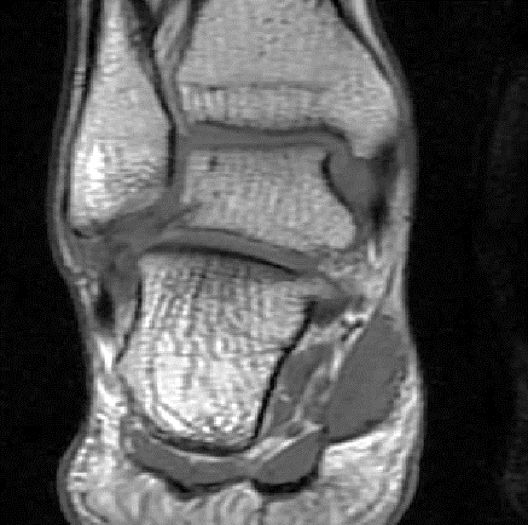

此片可以看到韧带结构消失,T2相高信号,整体韧带增粗,松弛,腓骨肌腱内侧,跟绯肌腱的形态完全消失,它的韧带也是松弛增粗的。所以考虑是踝关节距腓前韧带的损伤。